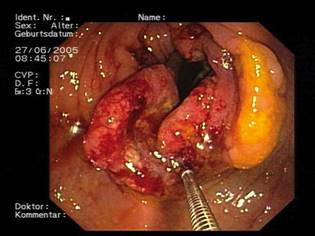

La pérdida de diferenciación por la que se caracterizan las células neoplásicas correlaciona con la poca o nula expresión de SERCA3 que se ha encontrado en cáncer de colon, estómago y células leucémicas. Las observaciones anteriores sugieren que la disminución en la expresión de SERCA3 es un evento temprano en el proceso carcinogénico, por lo que se evalúa su utilidad como marcador en el diagnóstico de distintos tipos de cáncer de origen epitelial.

Por otra parte, la disminución en la expresión de SERCA3 que se encontró en muestras de pacientes y líneas celulares de cáncer de colon y estómago se acentúa conforme aumenta el grado histológico de los tumores, que se estable según el estado de diferenciación de los mismos. Por lo tanto, el nivel de expresión de SERCA3 también puede ser útil en la estratificación de los tumores e incidir en el pronóstico del paciente según la abundancia en la expresión de esta proteína.